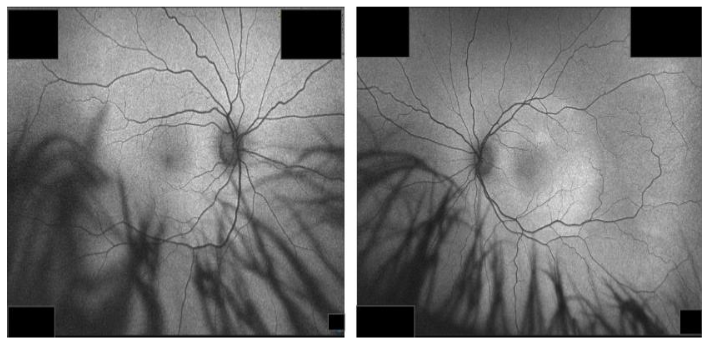

Five weeks later, the patient returned to the clinic with a visual acuity of 20/80-1 in the left eye that improved to 20/40-1 with pinhole. Intraocular pressure was 12 mm Hg in the right eye and 13 mm Hg in the left. Posterior segment exam demonstrated blunted foveal reflex of the left eye; right eye continued to appear within normal limits. Fundus fluorescein angiography was performed and showed a normal pattern in the right eye (Figure 3). Fluorescein angiography demonstrated a classic expansile dot pattern in the left superior macula consistent with CSCR (Figure 4).

Similarly, repeat autofluorescence imaging showed decreased hyperautofluorescence with diffuse distribution, indicating improvement (Figure 6).